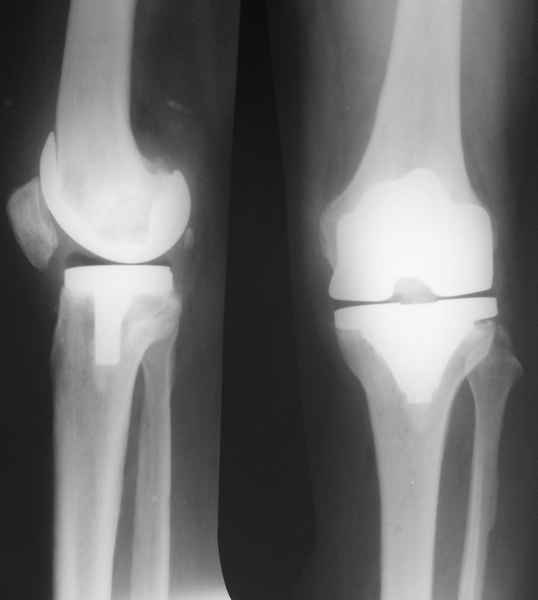

В феврале 2007 года пациентке выполнено эндопротезирование коленного сустава.

В июле 2007 года выполнена ревизия - полости сустава нет. Капсула сустава имеет толщину от 1 до 1.5 см, собственная связка надколенника имеет толщину до 3 см. Сустав заполнен фиброзно-рубцовой тканью. Компоненты стабильны.

Есть вопросы к установке протеза.

Скорее всего тибиальное плато было не конца резецировано и в задненаружных отделах осталась ступенька. Это привело к тому, что тибиальный компонент завалился на варус.

Можно пойти на повторную ревизию, удалить большеберцовый компонент и поставить его правильно, но как справиться с артрофиброзом?

Надо ли вести случай как нагноение с удалением протеза и установкой спейсера?